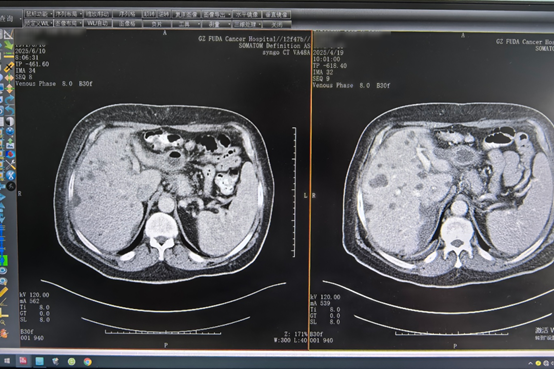

Setelah imunoterapi awal dan terapi target, Igor melaporkan pengurangan nyeri hati yang signifikan. Dua hingga tiga siklus kemudian, pemindaian CT menunjukkan pengurangan lesi pankreas dan beberapa metastasis hati. Tim medis Fuda segera menyesuaikan perawatannya dan melakukan krioablasi tumor hati. Di bawah bimbingan pencitraan, probe ablasi dimasukkan secara perkutan ke dalam tumor, di mana siklus pembekuan dan pencairan cepat digunakan untuk menghancurkan sel kanker secara tepat.